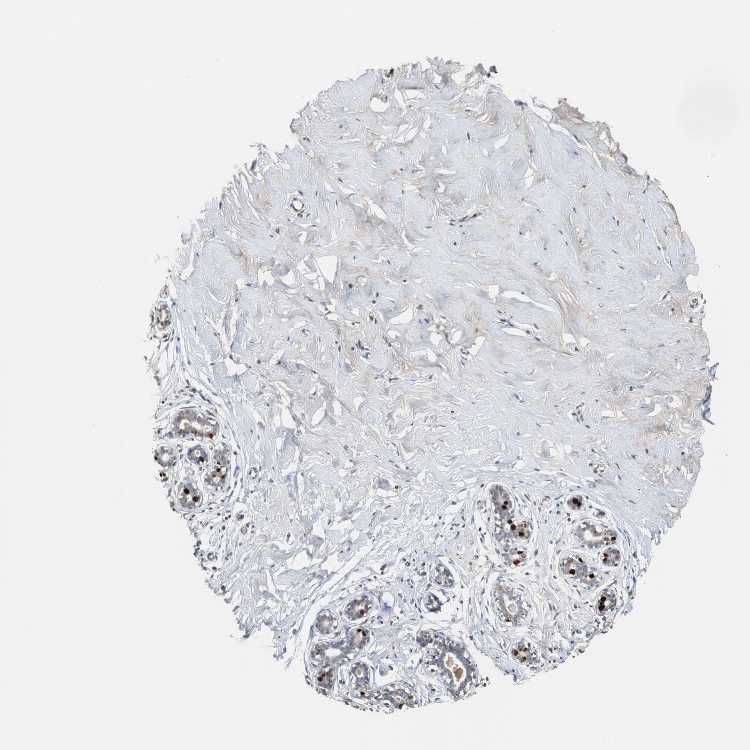

BREAST - Antibody stainingi

Antibody staining in the annotated cell types in the current human tissue is reported as not detected, low, medium, or high, based on conventional immunohistochemistry profiling in selected tissues. This score is based on the combination of the staining intensity and fraction of stained cells.

Each image is clickable and will lead to virtual microscopy that enables deeper exploration of all samples and also displays staining intensity scores, fraction scores and subcellular localization as well as patient and tissue information for each sample.

Antibody HPA006458Antibody HPA026773Antibody CAB002448

Adipocytes LowNot detectedNot detected

Glandular cells MediumNot detectedLow

Myoepithelial cells Not detectedLowNot detected